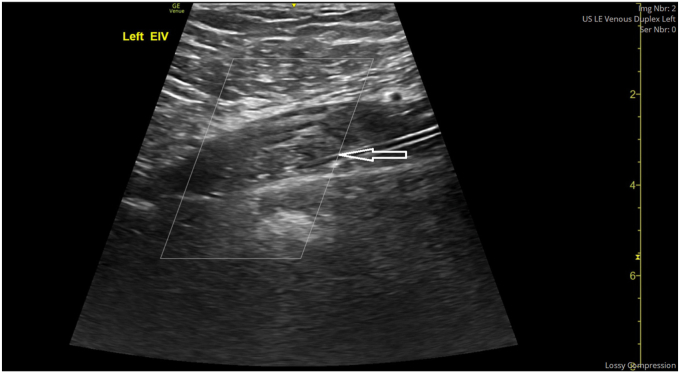

We present the case of a 20-year-old young man, with raised body mass index of >35 kg/m2, who was initiated on tirzepatide treatment for weight loss, with 12-kg weight lost over 6 weeks. The patient did not have any risk factors for thrombophilia including family history, any recent travel, immobilization, recent infections, or recent surgeries. He presented with left leg swelling, and physical examination revealed signs of proximal DVT, and ultrasound Doppler and computed tomography venography confirmed extensive left-sided DVT with complete obstruction of the common femoral and iliac veins. He underwent mechanical thrombectomy and was maintained on anticoagulation therapy. His investigations for thrombophilia screening excluded any other cause for DVT, with the etiology attributed to possibly rapid weight loss.